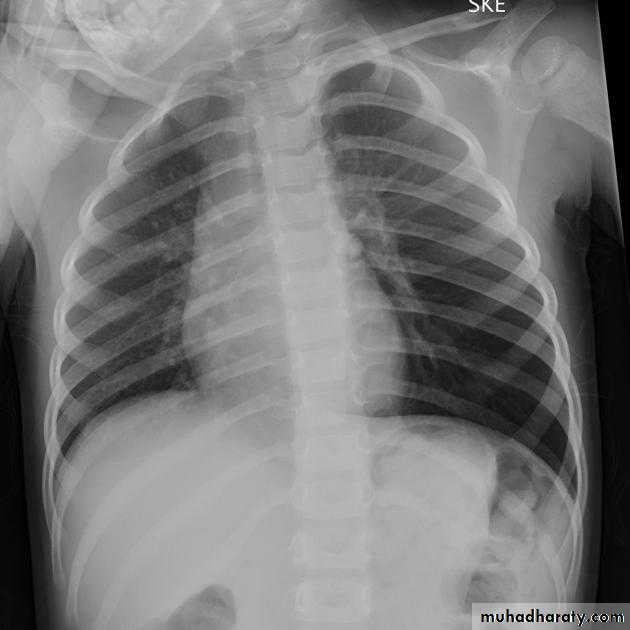

Post-primary pulmonary tuberculosis, also known as reactivation tuberculosis or secondary tuberculosis occurs years later, frequently in the setting of a decreased immune status. In the majority of cases, post-primary TB within the lungs develops in either :

* posterior segments of the upper lobes

*superior segments of the lower lobes

Typical appearance of post-primary TB

1.patchy consolidation or poorly defined linear and nodular opacities in both apices , upper zone in one lung , & lower zone in other lung ( ulternating lesion ) .2. Post-primary infections are far more likely to cavitate with multiple abscess formation & air fluid level more develop in the posterior segments of the upper lobes.

3. Tuberculomas seen in post-primary TB and appear as a well defined rounded mass typically located in the upper lobes .

4. Miliary tuberculosis is uncommon but carries a poor prognosis. It represents haematogenous dissemination of an uncontrolled tuberculous infection. It is seen both in primary and post-primary tuberculosis. Although implants are seen throughout the body, the lungs are usually the easiest location to the image. Miliary deposits appear as 1-3 mm diameter nodules . are uniform in size and uniformly distributed